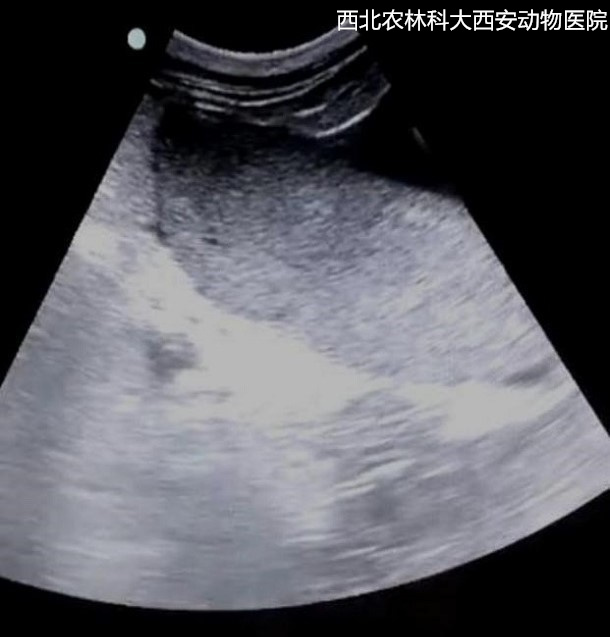

輔助檢查:腹部平片顯示腹腔有一中等密度占位性病變位于左下腹部,腹部器官邊緣銳利程度消失,腹部影像漿膜細(xì)節(jié)不能清晰可見(jiàn),胃和部分腸管積氣,提示腹腔積液、疑似占位待查見(jiàn)(圖1)。為進(jìn)一步診斷腹部占位的性質(zhì),對(duì)患寵進(jìn)行了超聲檢查,結(jié)果顯示腹腔間隙無(wú)回聲,腸管游離,腹腔肝后至膀胱有一非均質(zhì)、低回聲腫物,邊緣圓鈍,輪廓清晰,腫物內(nèi)部偶見(jiàn)低回聲病灶。提示腹腔積液、脾腫大且結(jié)構(gòu)異常,未見(jiàn)扭轉(zhuǎn),待查見(jiàn)(圖2)。

圖二